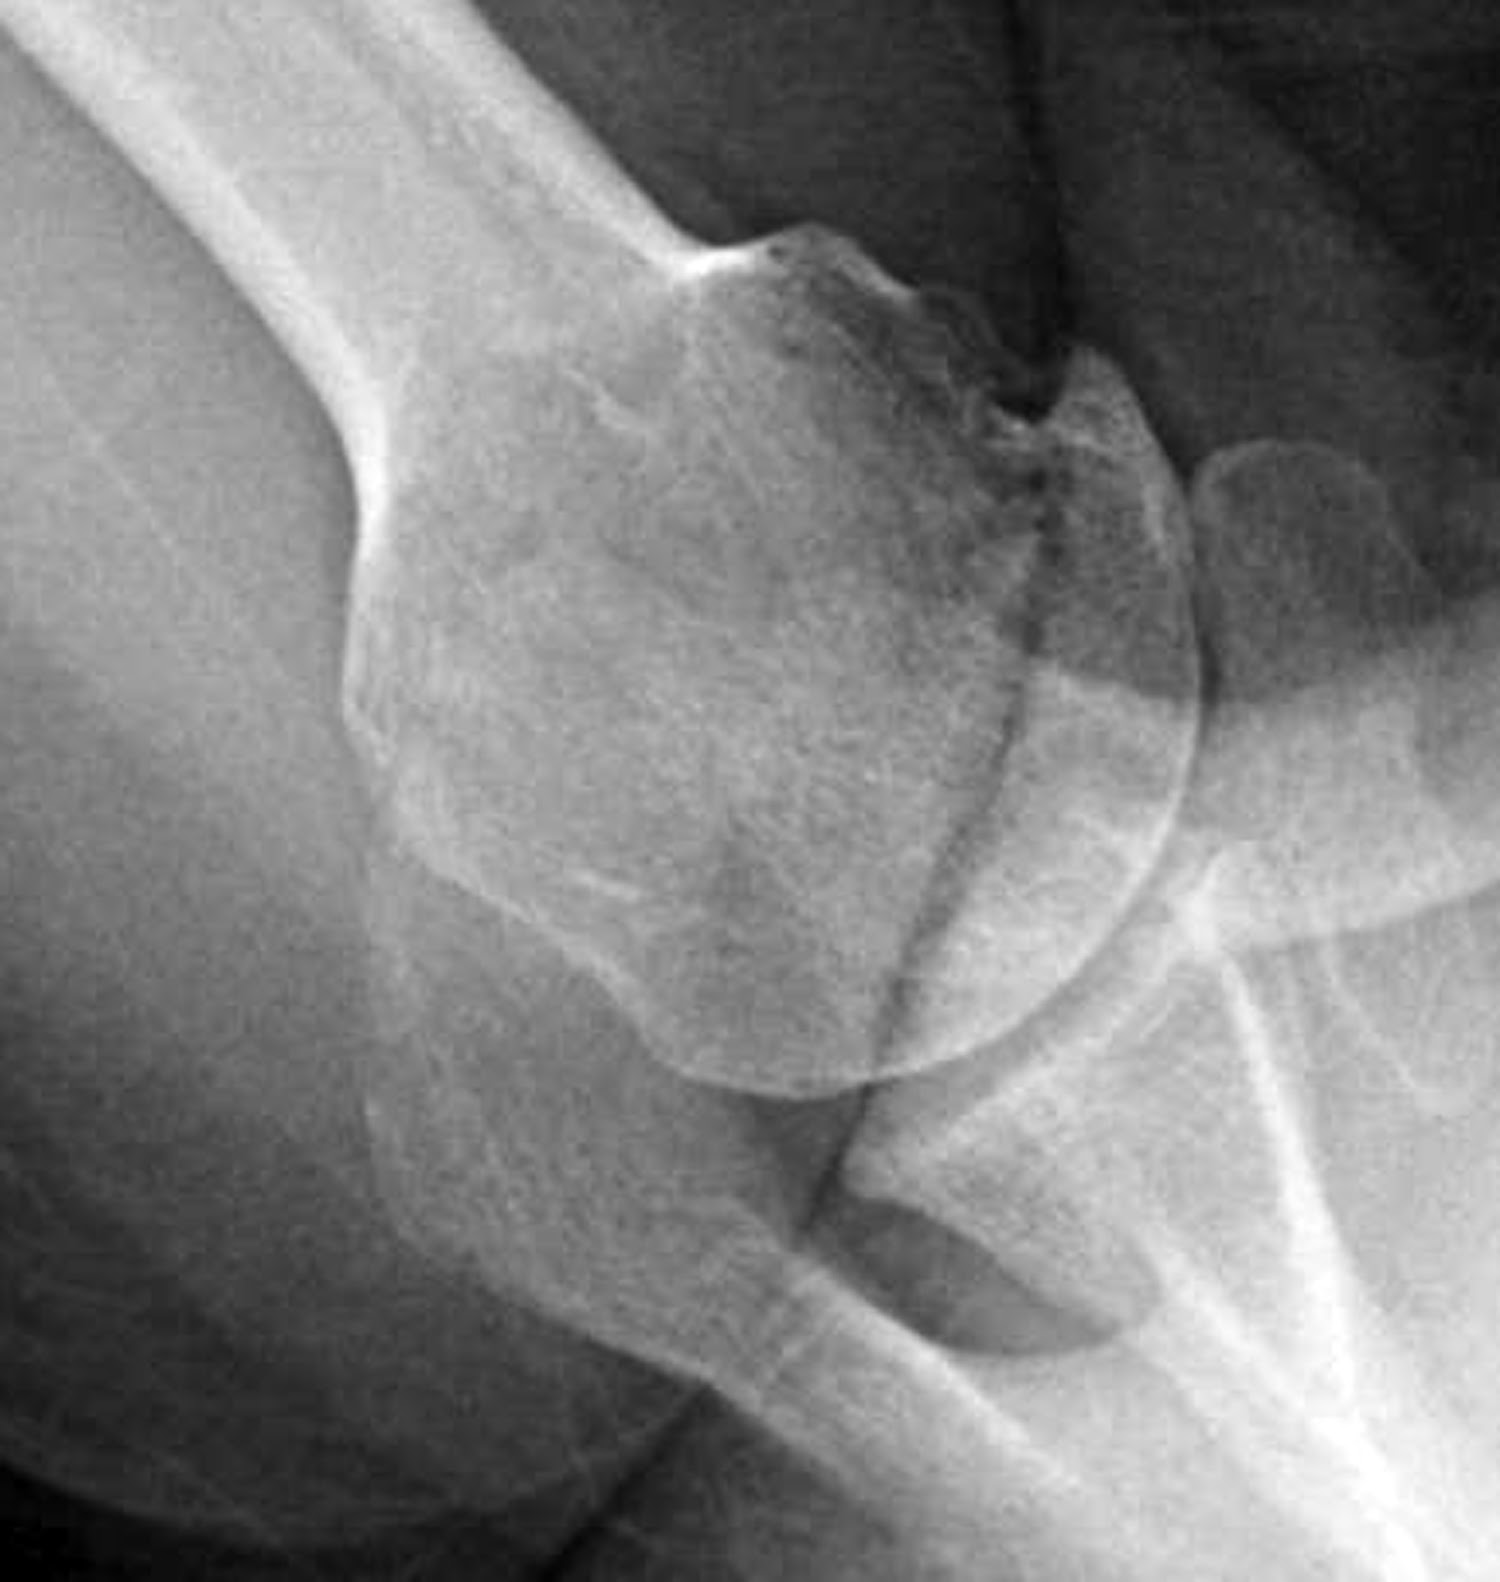

Unfortunately, many of the ‘axillary views’ sent to us on patients for consultation are taken without standardization, making it impossible to determine the important features of the glenohumeral joint as shown below.

The second key view is the axillary view taken with the arm in the functional position of elevation in the plane of the scapula and oriented so that both the spinoglenoid notch and the scapular neck are visible. This view shows a different perspective of the humeral anatomy, the amount of glenoid bone, the shape of the glenoid, its version in relation to the plane of the scapula and the relationship of the humeral head to the glenoid fossa. We have named the axillary view taken in with the arm elevated in the plane of the scapula the ‘truth’ view. This is because it demonstrates the glenohumeral relationships in the functional position of elevation; this is in contrast to CT scans, which have the disadvantage of being taken with the arm in the adducted position